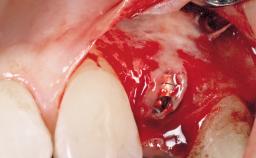

A 42-year-old female patient was referred to our clinic at the School of Dentistry of the University of São Paulo in November 2004, presenting a deficient restoration in the upper left central incisor. The clinical examination revealed no gingival retraction or any signs of gingival inflammation and, therefore, previous periodontal treatment was not considered. The patient presented a high lip line at full smile and a thin tissue biotype. This combination characterized a high-risk situation from an anatomic point of view, which required careful preoperative planning and cautious surgical execution.

Placement Protocol Immediate implant placement

Socket Integrity Sufficient, with intact bone walls

Bone Volume Sufficient, with intact walls